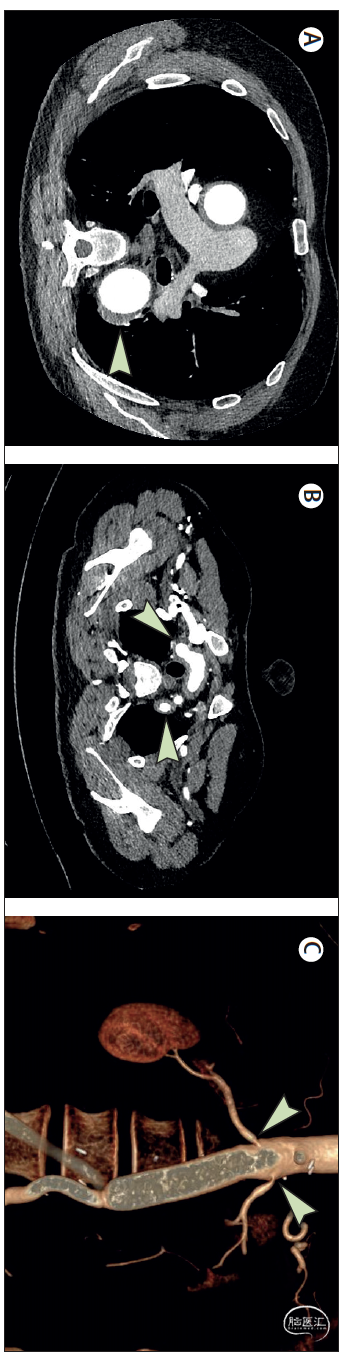

主动脉的结构变化可使用CT血管造影(图3)或磁共振血管造影进行评估。主动脉炎在CT血管造影上定义为环形管壁增厚(>2.2毫米)。近端大血管分支,如腋动脉、肾动脉、肠系膜动脉和髂动脉,也可观察到管壁增厚。磁共振血管造影(相对于CT血管造影)的优点在于无辐射,这对于病程中需要多次评估的年轻大动脉炎患者尤为重要,并且能够通过对比剂增强评估动脉炎症。除主动脉外,高分辨率磁共振血管造影已用于研究巨细胞动脉炎患者的颅血管和眼眶结构检查,汇总敏感性良好(81%),特异性高(98%)。对于新诊断的巨细胞动脉炎患者,即使是表现为颅动脉巨细胞动脉炎的患者,也建议使用CT血管造影或磁共振造影对颈部、胸部、腹部或盆腔血管进行无创成像,以检测和确定大血管受累的基线范围。

图3.大血管炎中的主动脉结构变化。本图展示了大血管炎患者的CT血管造影影像。(A)巨细胞动脉炎患者胸降主动脉瘤伴主动脉壁增厚(箭头所示)。(B)大动脉炎患者主动脉弓分支动脉壁增厚,尤其见于头臂干起始部、左颈总动脉及右锁骨下动脉(箭头所示)。(C)大动脉炎患者的腹主动脉三维重建图像,显示双侧肾动脉开口处狭窄(箭头所示),该患者曾接受主-双股动脉搭桥手术: